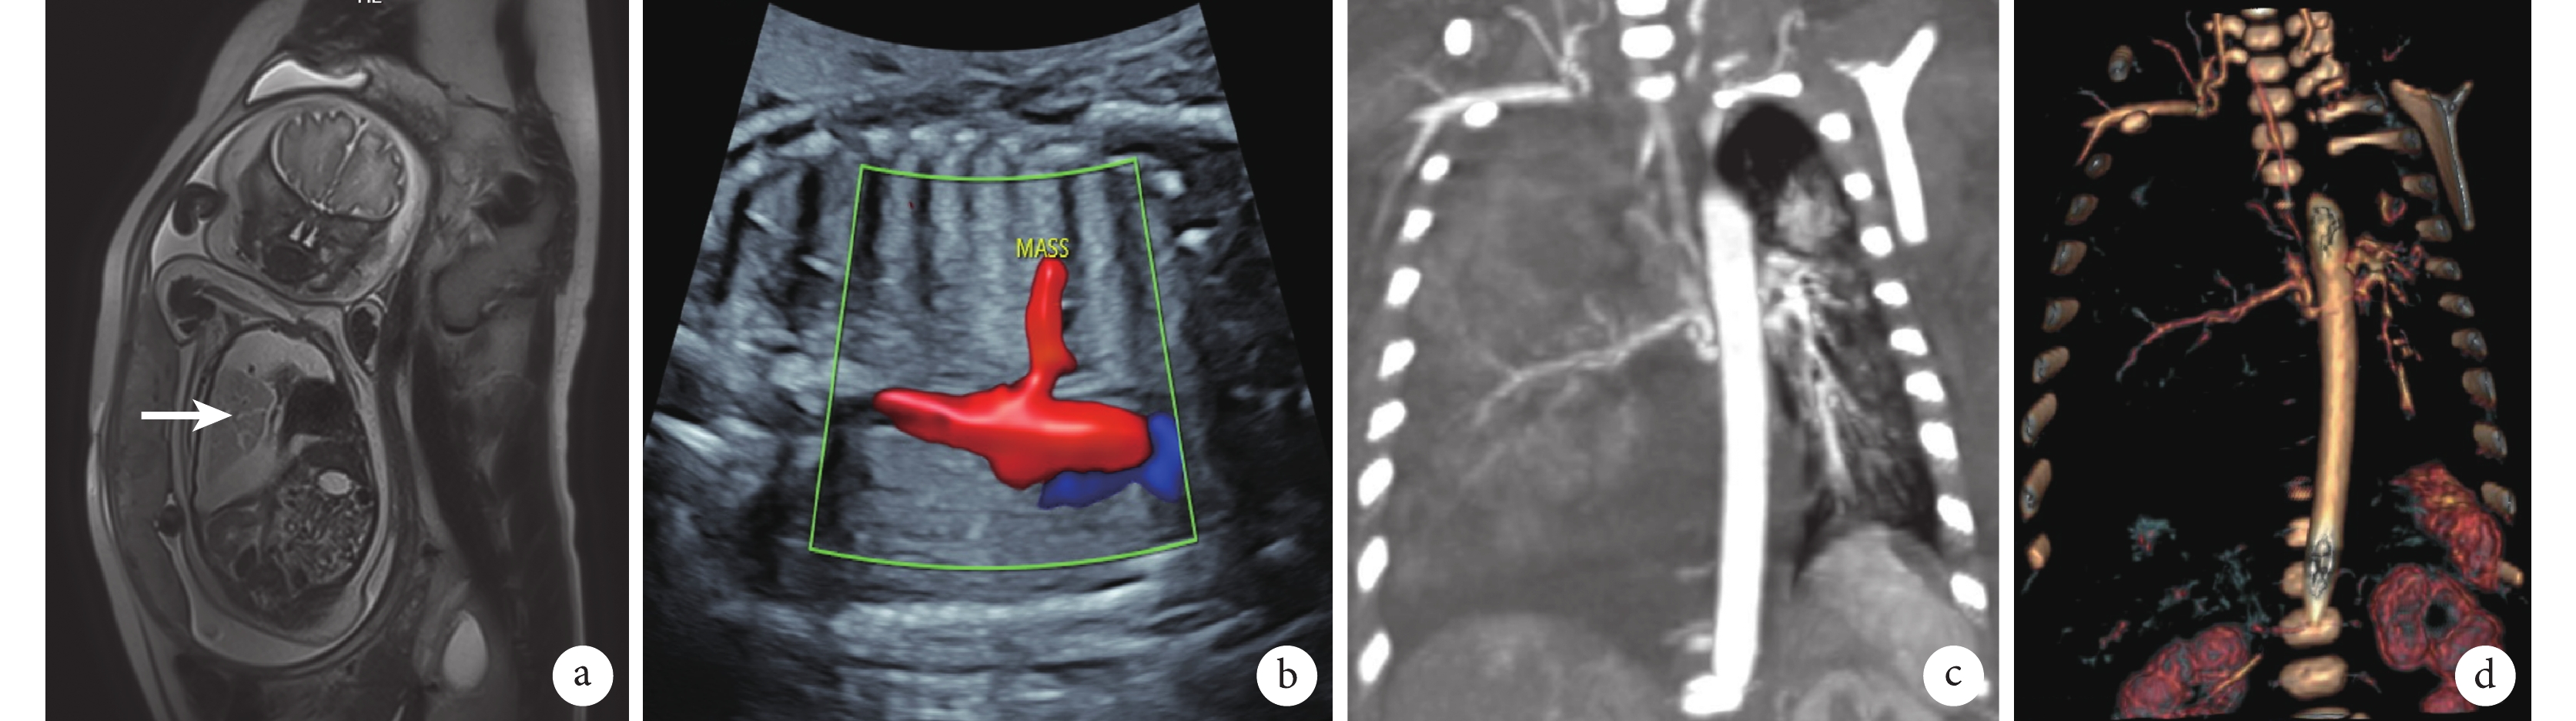

a:孕期核磁共振可見胎兒右側隔離肺大小約29×20×28mm(箭頭所示);b:宮內彩色超聲提示胎兒右側胸腔占位異常主動脈分支血供;c~d:新生兒胸部增強CT冠狀面示右側胸腔巨大占位及異常血供,血管三維重建提示異常血供起自胸主動脈

臨床資料 患兒,男,出生18 min,入新生兒科監護室。母親孕期定期產檢,孕23周時,孕期磁共振檢查發現胎兒右側胸腔占位,大小約29 mm×20 mm×28 mm,彩色超聲可見異常體循環血供,考慮隔離肺可能(圖1a~b)。定期產前檢查,右側隔離肺逐漸增大,同時合并雙側胸腔積液,右側為甚。孕33周時,右胸隔離肺大小約50 mm×32 mm×61 mm,胎兒右側胸腔積液增多,彩色超聲下液暗區約55 mm,予以宮內胎兒胸腔穿刺,抽約65 mL清亮液體,胸腔積液常規生化檢驗提示為漏出液。孕34周時,產檢提示右側胸腔大量積液,較前增多,右肺及縱隔受壓,經多學科會診討論后,予以宮內胸腔穿刺后急診行剖宮產手術。

患兒出生時體重2.55 kg,Apgar評分1 min 9分,5 min、10 min均10分。患兒出生后呼吸困難,三凹征,無明顯發紺,轉至新生兒科監護室。出生后1 d胸部增強CT(圖1c)顯示右側胸腔巨大占位及胸腔積液,血管重建可見腫塊內異常體循環血供(圖1d)。治療上,予以吸痰保持呼吸道通暢、面罩吸氧、預防感染、腸內營養、補液維持水電解質平衡、右側胸腔穿刺引流等對癥支持治療,患兒呼吸困難癥狀明顯改善。右側胸腔引流管,引流液約100 mL/d,持續引流,胸腔積液外觀呈油性,深黃色,Rivalta試驗陽性,乳糜試驗陰性。出生1周后,通過胃腸禁食及腸外營養,患兒胸腔積液性狀有明顯改善,由油性外觀轉為清亮胸腔積液,但積液量仍未見明顯減少。遂于出生后12 d行右側開胸探查,術中見胸腔大量淡黃色積液,右肺三葉發育良好,胸腔可見一暗紅色、包膜完整的隔離肺葉,有明顯的蒂(圖2a~b),起源于后縱隔,奇靜脈下方約1 cm處,手術予以結扎蒂部,完整切除隔離肺葉,術后病理學檢查示切除肺組織標本符合隔離肺表現(圖2c~d),留置胸腔引流管,術后第1 d引流約30 mL淡紅色液體,次日無明顯引流,復查胸部X線片患兒胸腔肺復張良好,無明顯積液。恢復腸內營養,右側胸腔仍無明顯積液引流,順利拔出胸腔引流管出院。